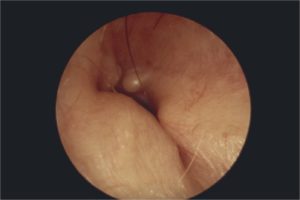

- استئوما و اگزوستوز (osteoma and exostosis): دو نوع رشد خوش خیم استخوانی هستند که می توانند در مجرای گوش خارجی ایجاد شوند. این دو بیماری از لحاظ علت، شکل، محل و درمان با هم تفاوت دارند. علت دقیق ایجاد استئوما و اگزوستوز مشخص نیست، اما برخی عوامل خطر ممکن است نقش داشته باشند. اگزوستوز معمولا به دلیل قرار گرفتن مکرر در آب سرد ایجاد می شود که باعث واکنش پری استئوم (غشای استخوانی) و رشد استخوان می شود. استئوما ممکن است به دلیل اختلالات ژنتیکی، التهابات، آسیب ها یا تومورهای دیگر ایجاد شود. اگزوستوز به صورت رشد های استخوانی صاف و گرد است که معمولا چندگانه و دو طرفه هستند. استئوما به صورت رشد های استخوانی ناهموار و مخروطی است که معمولا تکی و یک طرفه هستند. اگزوستوز معمولا در بخش داخلی مجرای گوش خارجی روی سطوح جلویی، پایینی و عقبی استخوان رشد می کنند. استئوما معمولا در بخش خارجی مجرای گوش خارجی روی استخوان رشد می کنند. درمان اگزوستوز و استئوما بستگی به شدت، علائم و عوارض آنها دارد. اگر رشد های استخوانی کوچک باشند و علائمی مانند درد، التهاب، ترشح، کاهش شنوایی و انسداد مجرای گوش خارجی ایجاد نکنند، ممکن است نیازی به درمان نباشد. اما اگر رشد های استخوانی بزرگ باشند و علائمی را ایجاد کنند، ممکن است نیاز به جراحی باشد. این جراحی می تواند باعث کاهش علائم و بهبود شنوایی شود، اما ممکن است خطراتی مانند عفونت، خونریزی، آسیب به پرده صماخ، تنگ شدن مجرای گوش خارجی و فلج صورت داشته باشد. بنابراین، جراحی باید با احتیاط و توسط پزشک متخصص انجام شود.

اگزوستوز